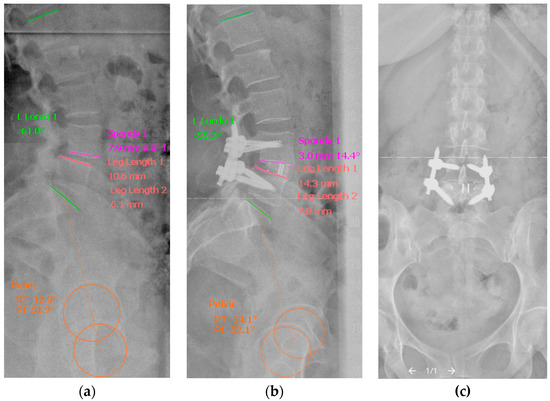

Figure 2.

Representative plain radiographs illustrating the measurement of the segmental, regional and pelvic sagittal radiographic parameters by Surgimap® (Version 2.3.2.1) on preoperative (a) and postoperative (b) standing lateral plain radiographs of the whole spine after MIS-TLIF and percutaneous pedicle screw fixation: segmental disc angle in degrees and spondylolisthesis in mm are measured by the “Spondy” tool; anterior and posterior disc height by the “LLength” tool; lumbar lordosis in degrees by the “LLordo” tool; and pelvic incidence, pelvic tilt and sacral slope in degrees by the “Pelvic” tool. A corresponding postoperative anterior–posterior projection of the lumbar spine (c).